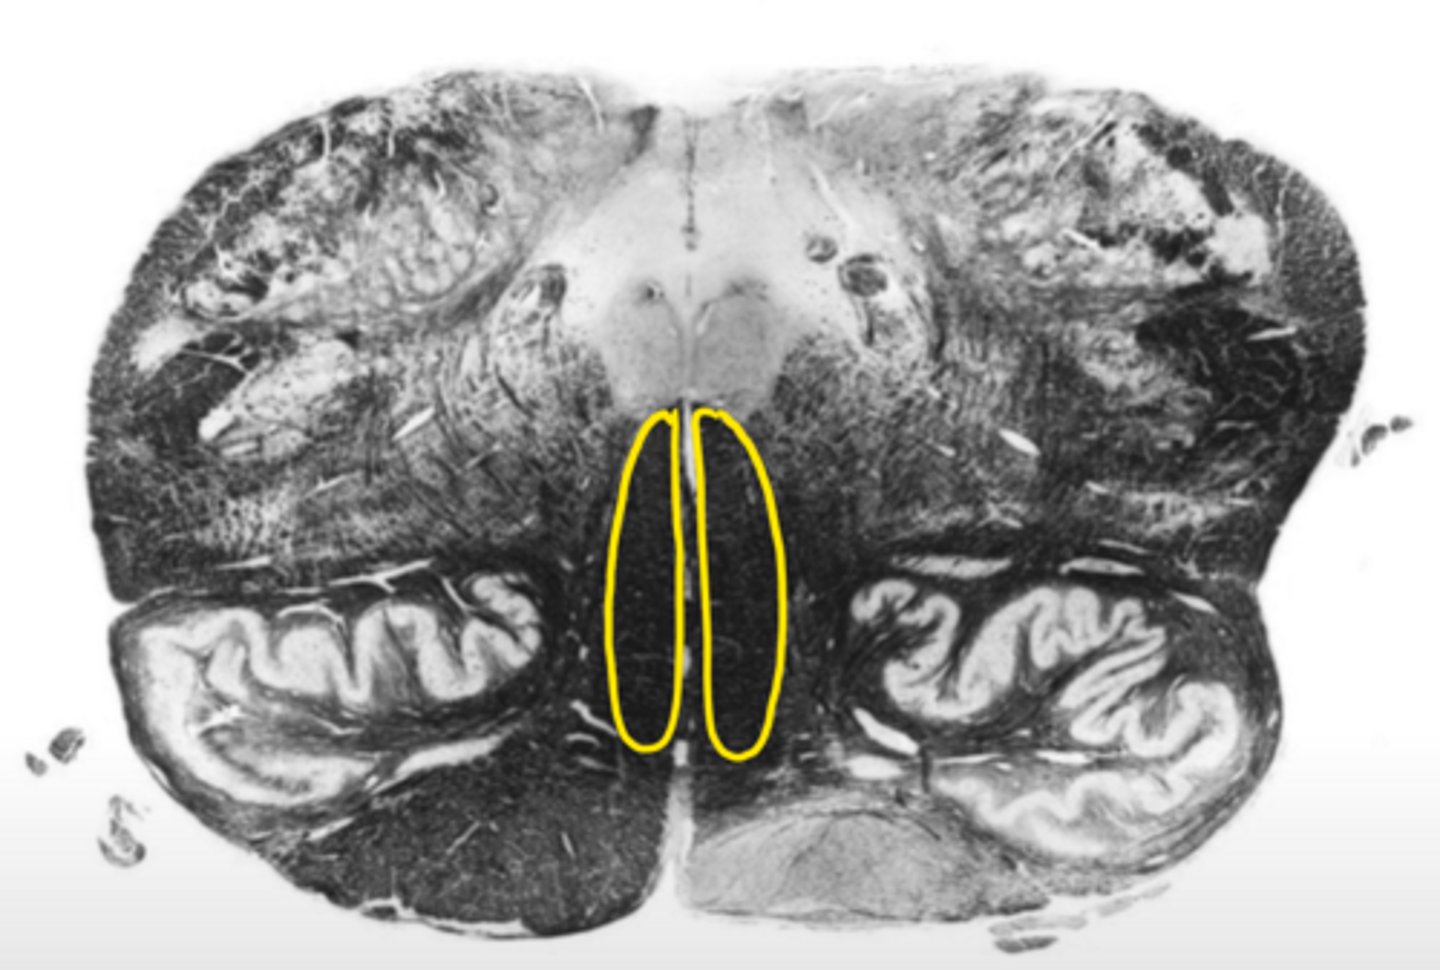

fourth ventricle

ID the space